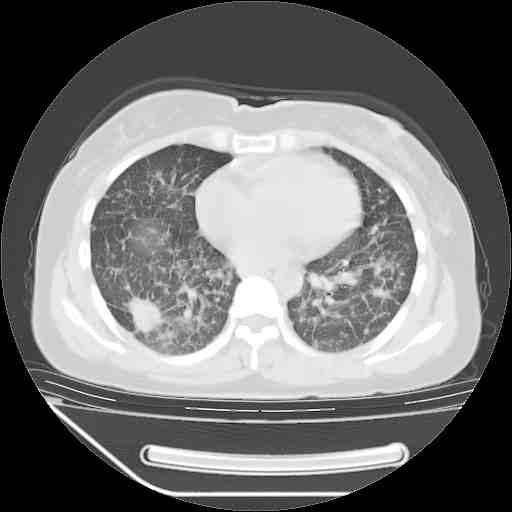

f50,肺ca治疗后,做过穿刺,确诊是肺ca,大家看看这是去年12月做的

考虑  腺癌肺内转移,治疗较前病灶缩小、减少

支持肺癌并肺内淋巴管转移,

肺癌并肺内转移,这种疾病治疗后在影像上看略有好转,不是很显著,但是肿瘤治疗效果影像只是一方面。

支持肺癌并肺内淋巴管炎,  原发灶小了,但转移较前片明显了.

支气管血管束粗而乱,考虑肺癌肺内淋巴管转移,右侧乳房第一二层软组织成份较左侧多,不会有问题吧?

支持右肺下叶周围型肺癌并肺内淋巴管炎,  原发灶小了,但转移较前片明显了.。

标准的细支气管肺泡癌呀!治疗后病情有所控制,也没治愈的迹象!